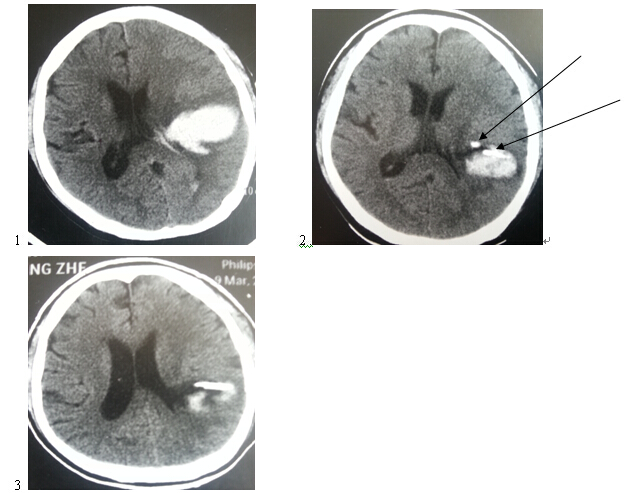

58岁男患,(1图术前定位CT,2图为术中CT,两箭头所示为两个引流管所在位置,3图为术后CT)